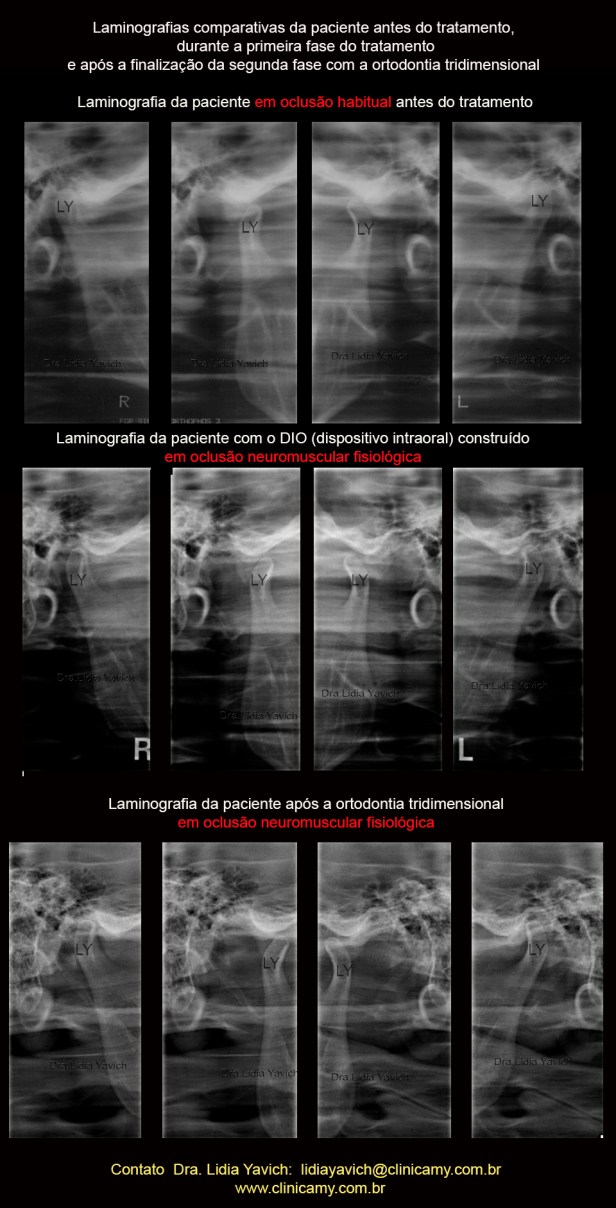

Laminografias comparativas da paciente: antes do tratamento, durante a primeira fase do tratamento e após a finalização com ortodontia tridimensional.

Laminografias comparativas da paciente: antes do tratamento, durante a primeira fase do tratamento e após a finalização com ortodontia tridimensional.